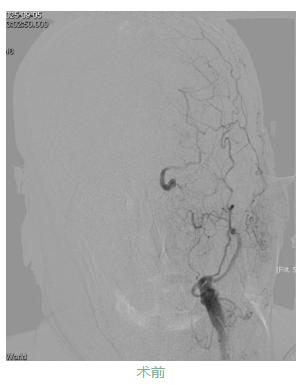

九旬的韩大爷因“言语不利、右侧肢体无力5小时”急诊入院,脑核磁显示左侧大脑半球大面积新发脑梗死,左侧颈内动脉急性闭塞。王振兴主任团队仔细研判影像发现:尽管梗死面积大,但缺血区域内仍有大量“可挽救的脑组织”——若能快速开通血管,韩大爷极有可能恢复独立生活能力。

家属透露,韩大爷2年前曾因左侧颈内动脉重度狭窄就诊于北京某医院,因血管走行极度迂曲、当时手术材料限制,未能成功植入支架。此次急性闭塞正是在“慢性狭窄基础上,因诱因导致急性闭塞”,缺血脑组织尚未完全坏死,但症状仍在持续加重。手术团队再次面临考验:韩大爷血管迂曲如“九曲十八弯”,基础病多,术中稍有不慎便可能引发致命并发症。

凭借丰富经验与先进介入技术,医生精准操控导管、导丝,克服重重障碍,历经2个多小时成功开通闭塞血管,并顺利植入一枚支架。术后第2天,韩大爷右侧肢体功能显著恢复,经过半个月综合治疗,目前已转入康复阶段,生活自理能力逐步提升。